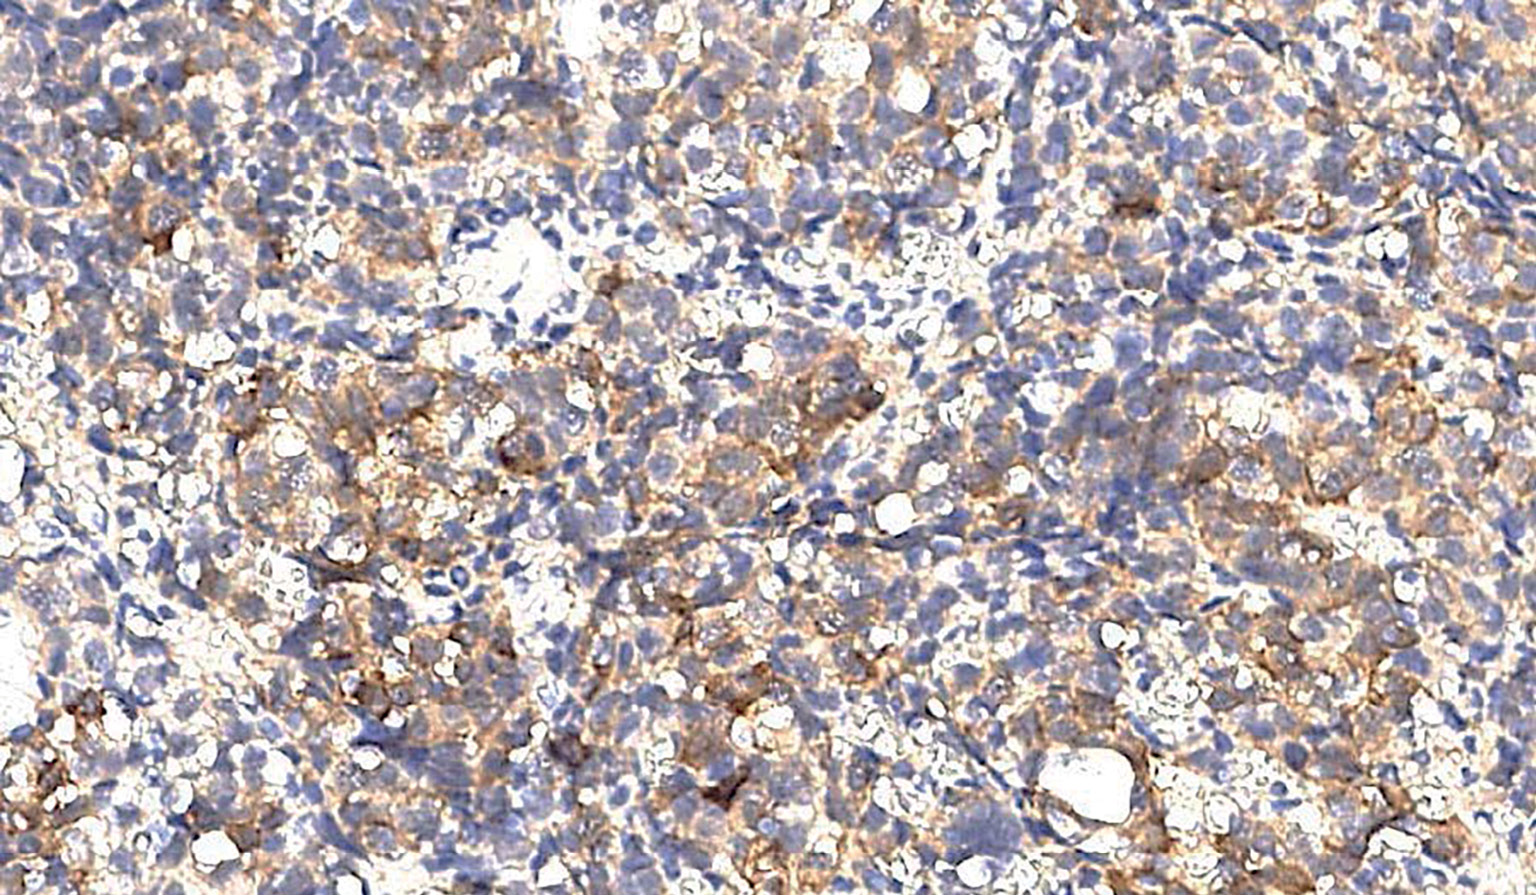

Группа фМЭН 1 показала значительно большую цитоплазматическую экспрессию менина (рис. 1), чем в группе гМЭН 1 (p=0,006). Группа гМЭН 1 также отличалась от группы СА по экспрессии менина: ядерной окраски в группе 1 не было выявлено ни в одном случае (рис. 2), обнаруженная цитоплазматическая экспрессия менина в 3 образцах была слабой степени выраженности, в одном — средней (p=0,012) (рис. 3).

Рисунок 1. Цитоплазматическая экспрессия менина в образце ткани аденомы гипофиза у пациента с фенокопией синдрома множественных эндокринных неоплазий 1 типа, х200.